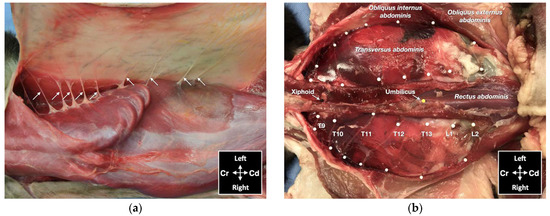

One male and one female cat weighing 4.1 and 3.7 kg, respectively, were studied. The observed anatomy of the abdominal wall musculature and innervation is shown in Figure 4. The belly of the m. transversus abdominis extended through almost the entire abdominal cavity, ended at half of the width of the m. rectus abdominis and extended in a thin aponeurosis to the linea alba. The belly of the m. obliquus internus abdominis, which was found between m. transversus abdominis and the m. obliquus externus abdominis, ended at the mid-width of the hemiabdomen (at about 1 cm lateral to the mammary glands line) and extended in a long aponeurosis to the rectus sheath. The m. obliquus externus abdominis is found along the lateral and ventral part of the abdomen, ending with the most superficial aponeurotic layer of the rectus sheath. Finally, the m. rectus abdominis extended longitudinally in the ventral abdominal wall from the external surface of the thorax to the pubic bone and it is enclosed in the rectus sheath, which multilayered aponeuroses were difficult to dissect. In one cat more than the other, a layer of adipose tissue was observed beneath and immediately caudal the costal arch, between the mm. rectus abdominis and transversus abdominis, extending laterally between the mm. obliquus externus and internus abdominis. The ventral branches of the spinal nerves T9–L3 were identified in both cadavers. These branches were further divided into ventrolateral and ventromedial branches. The ventrolateral branches were located at half of the width of thorax and abdomen (Figure 5a). These branches are found between the intercostal muscles or between the mm. obliquus internus abdominis and obliquus externus abdominis, before they end at the subcutaneous and cutaneous tissues. The ventromedial branches were located within the TAP, with different endings: the T9 branch at the lateral margin of the xiphoid process, T10–L2 at the ventral midline (with T12 and T13 being cranial and caudal to the umbilicus, respectively) and further divided into terminal branches in the belly of m. rectus abdominis, and L3 in the belly of the m. transversus abdominis at the level of the pubis (Figure 5b).

Figure 5. Gross anatomical dissection of two cat cadavers: (a) the lateral cutaneous branches of thoracic (T) and lumbar (L) spinal nerves are indicated by arrows; (b) the ventromedial branches of the spinal nerves from T9 to L2 are indicated by white pins; Cd, caudal; Cr, cranial.